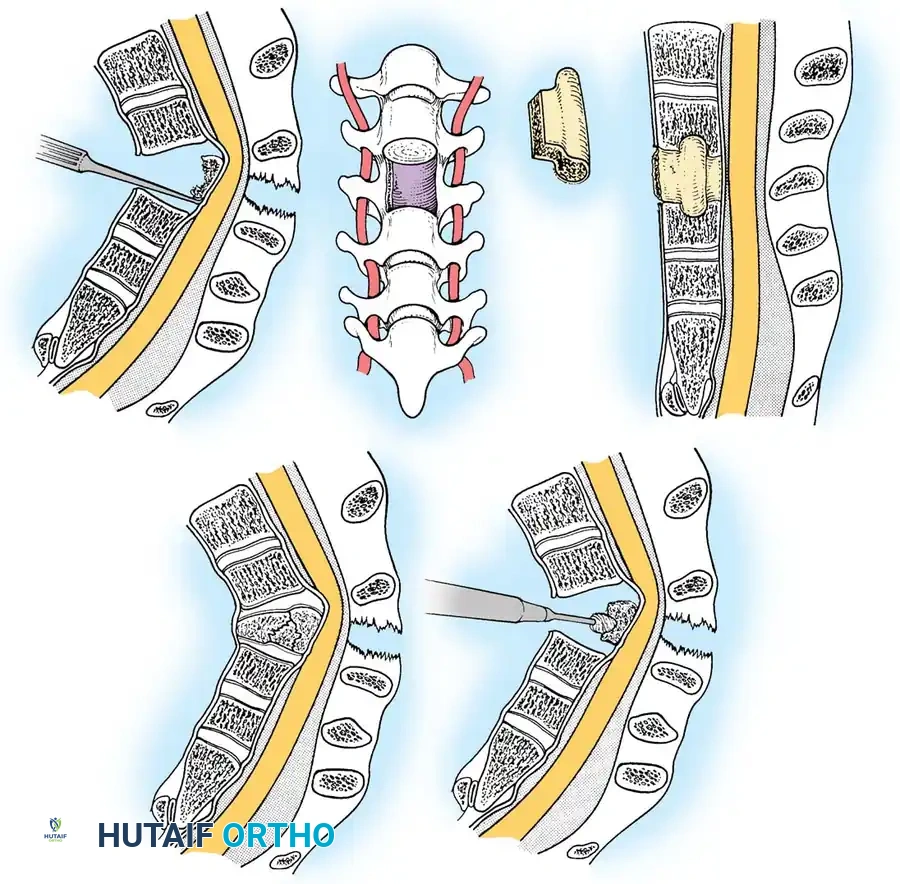

Anterior Cervical Discectomy and Fusion (ACDF)

Indications: Anterior column compromise, extruded traumatic disc herniations, or as the first stage in a 360-degree fusion for severe distractive flexion injuries.

Surgical Steps:

1. Exposure: Retract the longus colli muscles laterally to expose the anterior vertebral bodies and the damaged disc space.

2. Discectomy: Perform a complete discectomy using curettes and pituitary rongeurs. In trauma, the PLL is often torn; carefully remove any extruded disc fragments compressing the cord.

3. Endplate Preparation: Decorticate the cartilaginous endplates using a high-speed burr to expose bleeding subchondral bone, ensuring a robust fusion bed.

4. Grafting: Insert a structural allograft or PEEK cage packed with autograft/demineralized bone matrix (DBM) into the disc space.

5. Plating: Apply a rigid anterior cervical plate. Ensure screws are placed parallel to the endplates and do not breach the adjacent disc spaces.

Posterior Cervical Fusion (PCF) and Instrumentation

Indications: Posterior tension band failure, irreducible facet dislocations requiring open reduction, or multi-level instability.

Surgical Steps:

1. Open Reduction: If a facet is dislocated, carefully lever the inferior articular process of the superior vertebra over the superior articular process of the inferior vertebra using a Penfield elevator.

2. Lateral Mass Screw Fixation:

* Utilize the Magerl or Roy-Camille trajectory.

* Magerl Technique: The entry point is 1 mm medial and 1 mm superior to the center of the lateral mass. The drill is angled 25 degrees laterally (to avoid the vertebral artery) and 15 degrees cephalad (to avoid the exiting nerve root).

3. Rod Contouring: Contour titanium or cobalt-chrome rods to match the patient's natural cervical lordosis and secure them to the screw heads with set screws.

4. Decortication and Fusion: Aggressively decorticate the lateral masses and facet joints with a high-speed burr. Pack the gutters with cancellous autograft (often harvested from the iliac crest) or high-quality allograft.